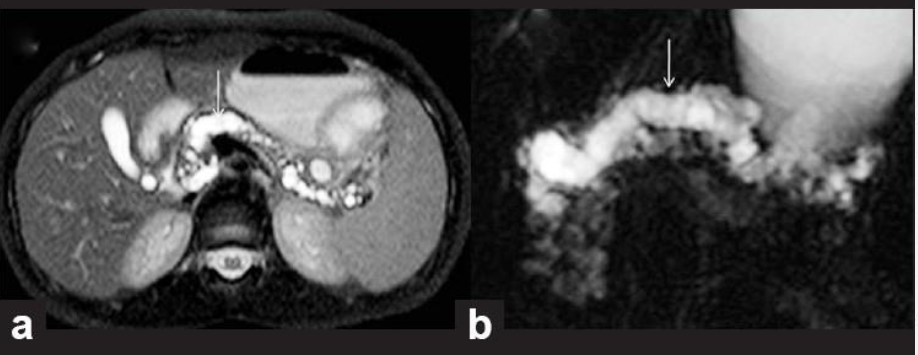

Q

מהו הממצא

A

IPMN

הרחבה של צינור הלבלב יחד עם ציסטה, מדובר בציסטה גידולית